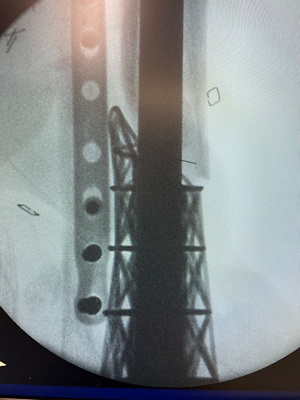

So just how does the Eiffel Tower procedure work? “We conduct a CT scan of the injured limb and look at the shape of the bone that’s missing,” explains Dr Birkholtz. “We model that in three dimensions and in consultation with a biomedical engineer, and through the use of a 3D printer, we create a titanium truss cage that looks like the Eiffel Tower. The cage is then fixed to the surrounding bone and tissue. It’s basically a structure that takes over some of the function of the bone but because we pack the structure full of bone graft, it incorporates into the bone as well, becoming a permanent fixture and replacing that segment of bone that is missing.”

The custom 3D-printed truss cage reconstruction is a viable alternative. While Dr Birkholtz did not invent the procedure, he’s dubbed it the Eiffel Tower due to the shape of the cage. “It’s exciting because it gives us another salvage option which we can use in very difficult bone reconstruction cases,” he says. “This option that could also potentially reduce the group of those requiring amputation.”